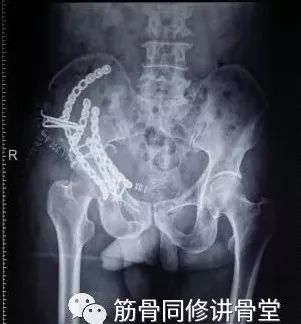

2)骨盆骨折

30min,三个决定:

- 开放性骨折,立即止血;

- 骨盆制动(10-15min);

- 观察10-15min,血流动力不稳定,能否手术?

血流动力学稳定,在7天内手术?

3)髋臼骨折(伤后5-7天)

- 人体最大的负重关节,精确复位可达到关节的最佳匹配,确保正常力学性能;

- 影像学移位程度大,不匹配>2mm--手术;

- 髋关节脱位,髋臼后壁骨折并股骨头骨折,复位后关节仍然不稳,或关节腔有游离骨块--手术。

并发症:异位骨化18-90%;股骨头坏死3-9%